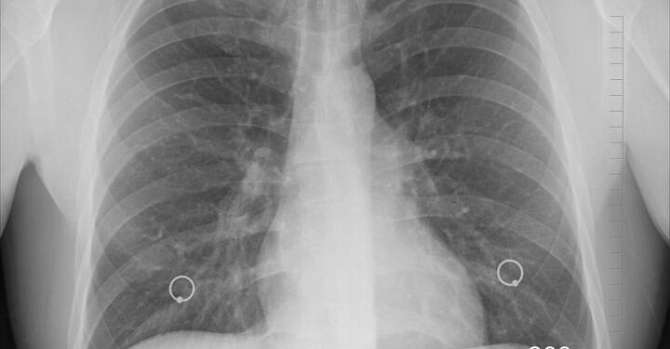

Признаки болезни могут быть разными: от полного отсутствия симптомов до выраженных респираторных (кашель с мокротой или сухой, кровохарканье, одышка) и общих интоксикационных (лихорадка, ночная потливость, похудение, усталость) жалоб разной степени выраженности.